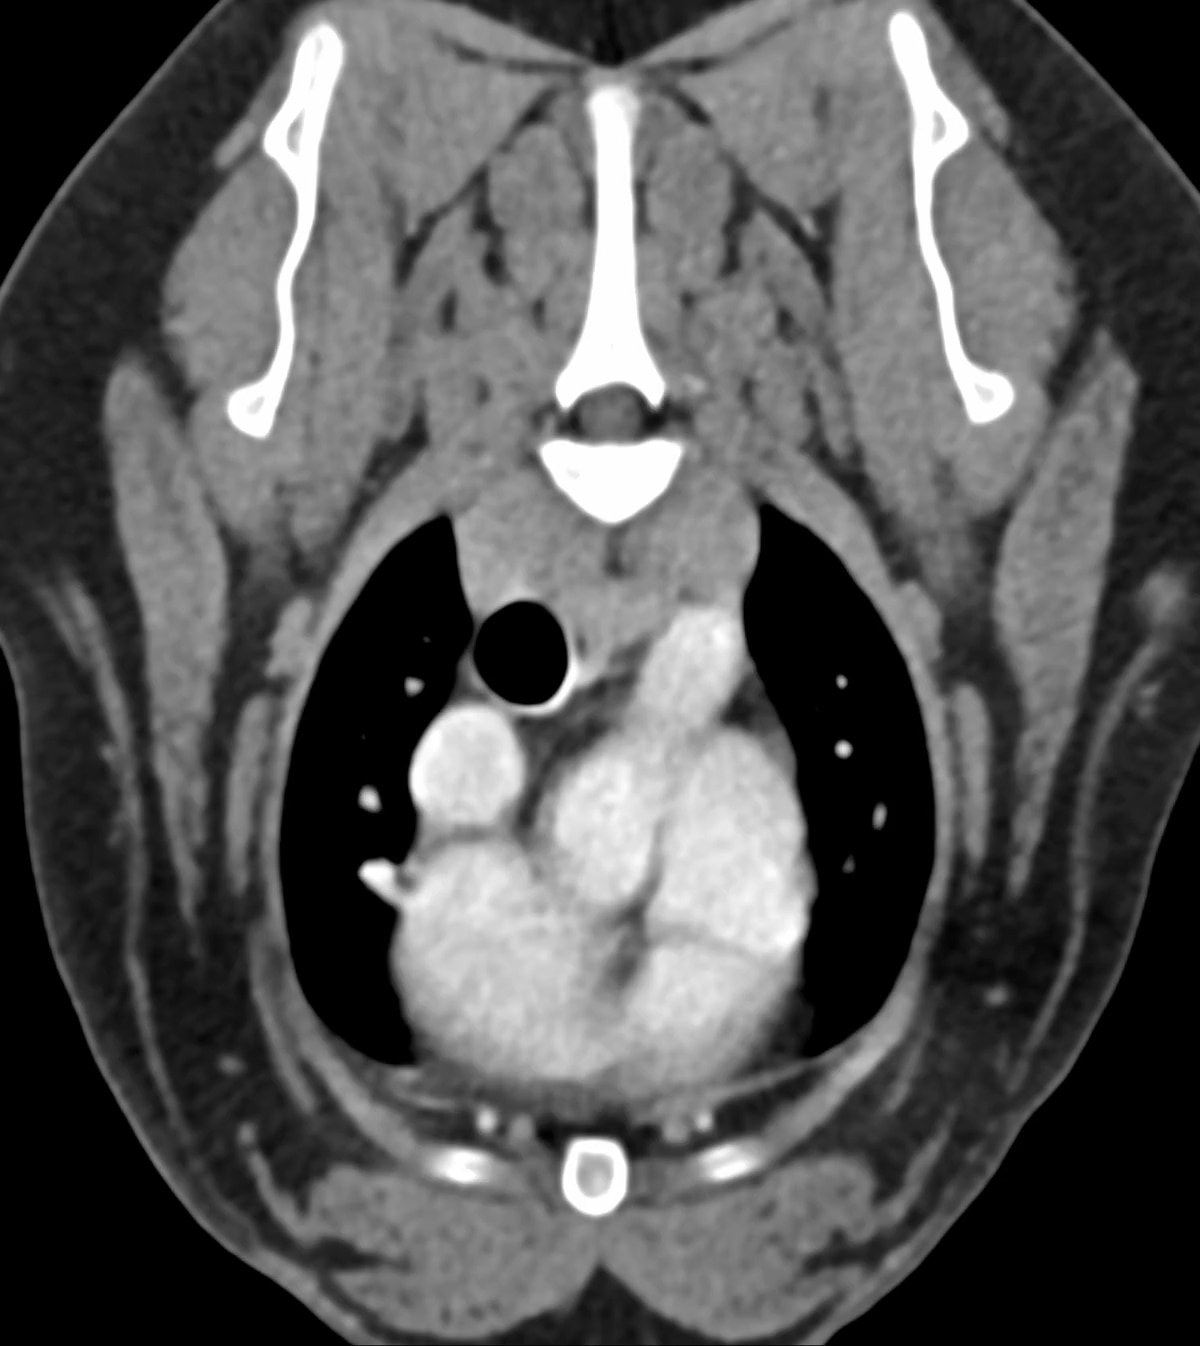

CT-Studie von Mai 2025. Die dargestellte Raumforderung an der Herzbasis war zum Untersuchungszeitpunkt klinisch asymptomatisch.

CT-Untersuchung von Freya: Gut begrenzte, ovoide Raumforderung mit heterogener Kontrastmittelanreicherung (türkise Pfeile) an der Aufzweigung der Pulmonalarterien (PA).

In der CT-Untersuchung von Freya zeigt sich eine umschriebene, hypervaskularisierte Raumforderung an der Aufzweigung der Pulmonalarterien mit heterogener Kontrastmittelanreicherung. Die gut begrenzte, ovoide Raumforderung ist heterogen weichteilattenuiert und im Durchmesser ca. 2,6 cm groß.